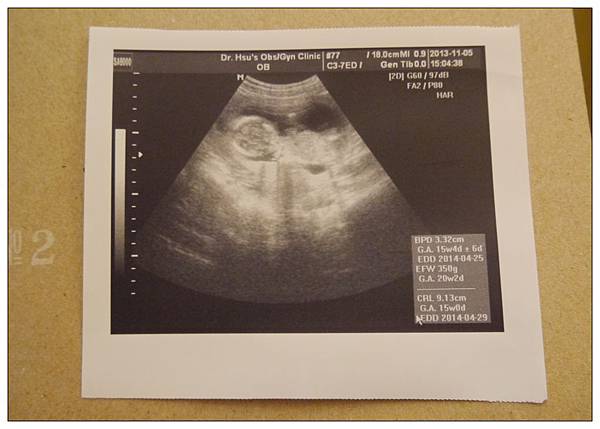

這次蔡小球已經滿15W~身長9.13公分~體重是350g~~

嗯~~大概是一罐大瓶多多那麼重??XDD

預產期跟醫生之前算的時間差不多~就是在明年的四月底左右